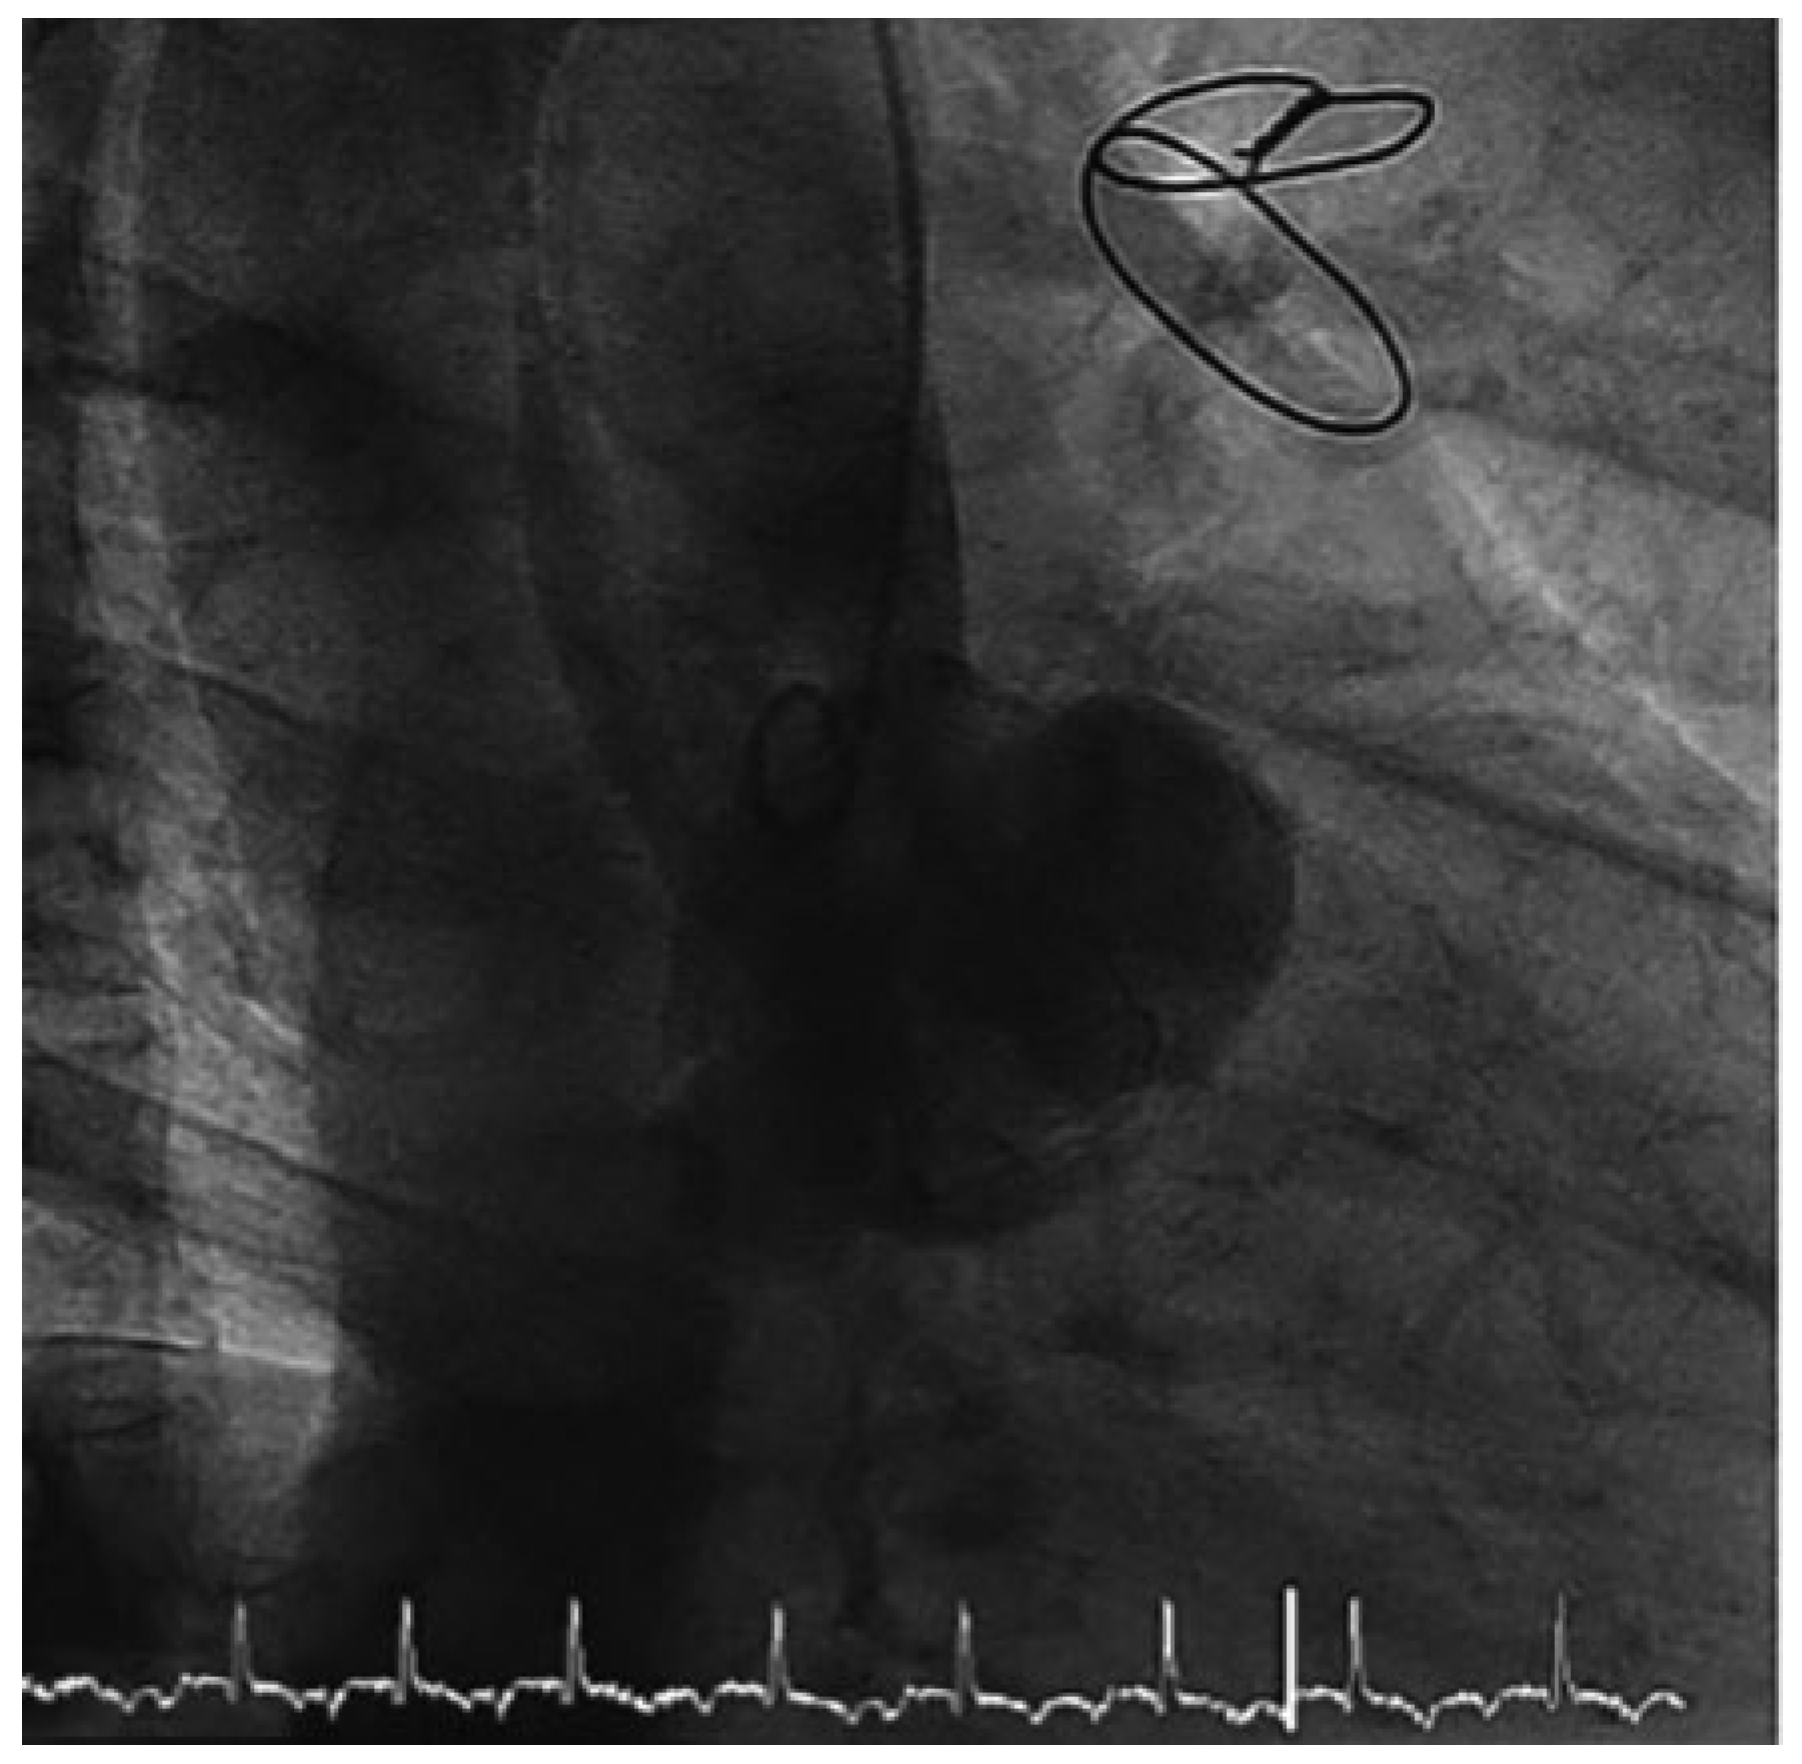

In this case the involvement of an endocarditis team was necessary to coordinate the following therapy. One week after adjustment of the antibiotics to penicillin, according to sensitivity analysis of the bacterium, the knee endoprosthesis was explanted in total. During the operation we performed a TOE, which showed an increase in the vegetation length to 1.6 cm. The following day preoperative diagnostic tests including computed tomography for exclusion of septic embolism and coronary angiography were performed (Figure 2). The patient was scheduled for cardiac operation 3 days after explantation of the knee prosthesis. Surprisingly, concerning cardiac complaints, the patient remained oligosymptomatic.

Figure 2. Coronary angiography: Contrast medium shows an enlargement of the aortic root without insufficiency.